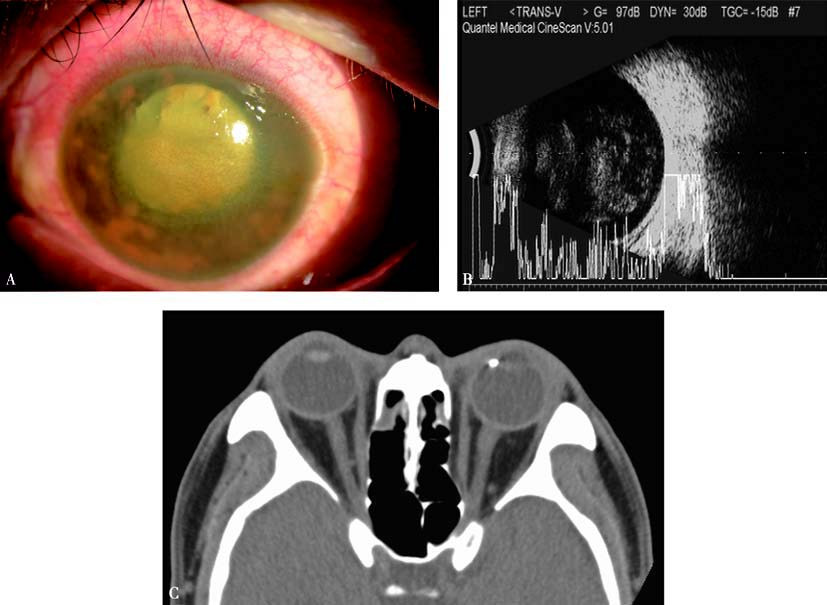

Figure 1 Ocular siderosis

A. Anterior segment of the left eye shows mild corneal opacity, iris heterochromia with rust-colored deposits on the iris surface, dilated pupil, and lens opacity.

B. A/B-scan ultrasound demonstrates vitreous opacities.

C. CT imaging shows a metallic foreign body near the nasal-side ciliary body of the left eye.